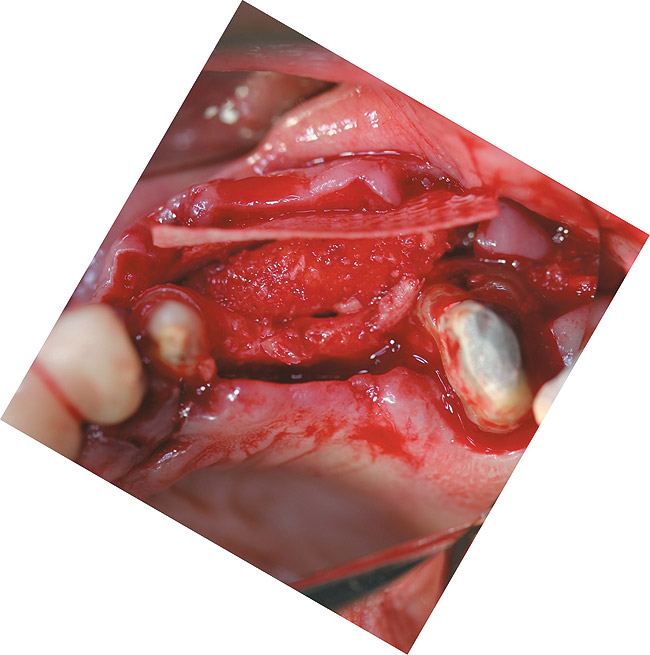

A full-thickness incision was made. Flap reflection revealed a narrow residual ridge with significant apical undercuts (Figure 8). Regenaform® paste (Exactech, Inc, www.exac.com) was molded on the buccal aspect of the ridge, as well as crestally. A 20-mm x 30-mm Ossix Plus membrane was trimmed and adapted to cover the graft material (Figure 9). Periosteal releasing incisions were made, and passive primary closure was obtained.

Figure 9 The Regenaform paste molded to the ridge, and the Ossix Plus resorbable membrane ready for positioning over the graft material.

Figure 9